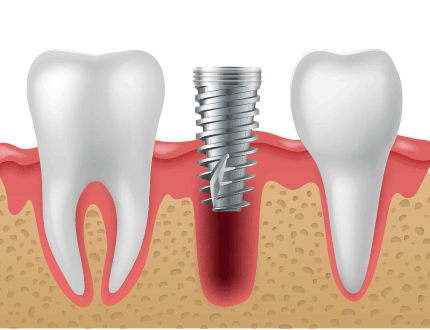

발치즉시 임플란트는 말그대로 보존이 불가능한 치아를 발치하자 마자 치아를 발치한 곳에 임플란트를 식립하는 술식을 말합니다.

발치 즉시 임플란트는 문제치아를 발치한 당일 바로 임플란트를 식립함으로써 여러 번의 시술, 마취에 대한 부담감이 적고

치료기간을 단축할 수 있는 고난이도 시술법입니다.

발치 후 즉시 임플란트를

식립하면 주변 잇몸 조직의

손상을 최소화할 수 있습니다.